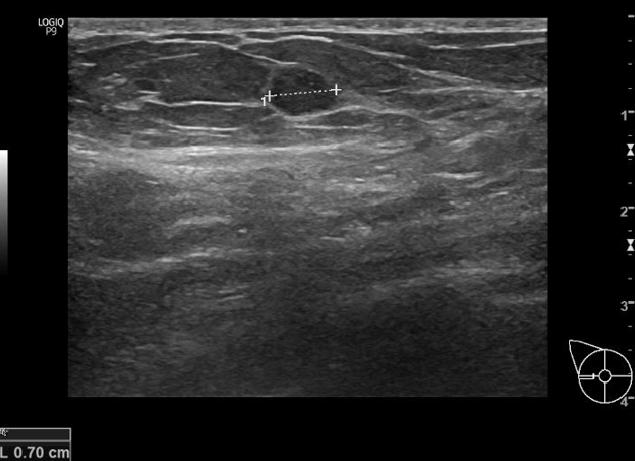

Гипоэхогенное образование на мониторе ультразвукового аппарата выглядит как затемненное пятно. Его форма различна, зависит от типа уплотнения. Контур может быть смыт или четко виден.

Гипоэхогенное образование в молочной железе на УЗИ

Термин «гипоэхогенное образование» не означает конкретную патологию. Темные области, которые видны на УЗИ, указывают на разницу плотность тканей в определенных участках. Здоровые ткани обозначаются серым цветом, а с низкой плотностью могут быть затемненные или черные. Это говорит о патологическом процессе, протекающем в груди.

Гипоэхогенные образования на мониторе видны отчетливо, но контуры могут быть смазаны. Чаще области с пониженной плотностью обнаруживаются при плановых осмотрах.

Благодаря методу УЗИ, можно диагностировать состояние молочных желез. Если во время такой процедуры было выявлено гипоэхогенное образование, то это значит, что на снимке эта область будет показана более темным участком на светло-сером фоне. Скорость движения ультразвука на месте такого образования будет медленнее, чем в любом другом пространстве.

Во время проведения УЗИ они на общем фоне отличаются по оттенку ― здоровые участки обозначаются светло-серым цветом, а гипоэхогенные являются более темными. Для максимально точной диагностики такого состояния, опытный доктор должен провести тщательное обследование.

Обнаруженное во время УЗИ такое образование представляет собой зону с пониженной акустической активностью.

Гипоэхогенное образование на УЗИ

Ее главными отличительными признаками являются более:

- затемненный оттенок структуры тканей по сравнению с соседствующей областью;

- медленное продвижение ультразвуковых волн.